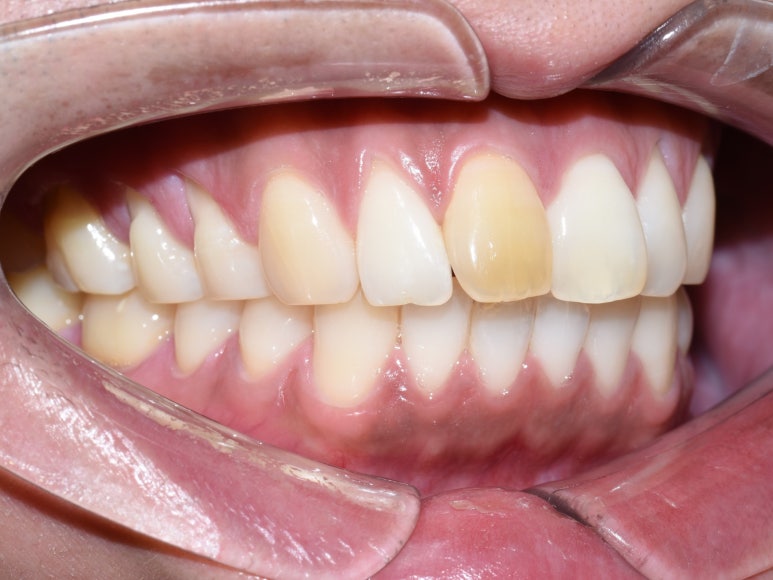

또 다른 환자의 케이스 입니다.

오래 전에 신경치료도 한 치아인데 변색이 되었다고 하셨습니다

배열도 보시다시피 튀어나와있는 상태였습니다.

단 두 번의 내원으로(일주일 소요)

환자분 의 컴플렉스를 고칠 수 있게 되었습니다

앞니 하나 크라운을 통하여 색깔도 변화 시키고 튀어나온 것도 들어가게 만들 수 있었습니다

원장님께서는 약간 색이 티가 나는 거 같다며

한 번 더 완벽하게 수정 하는 게 어떻겠냐고 하셨지만

환자 분이 너무 쿨 하셔서 이 크라운에 만족 한다며 크라운을 붙이고 가셨습니다